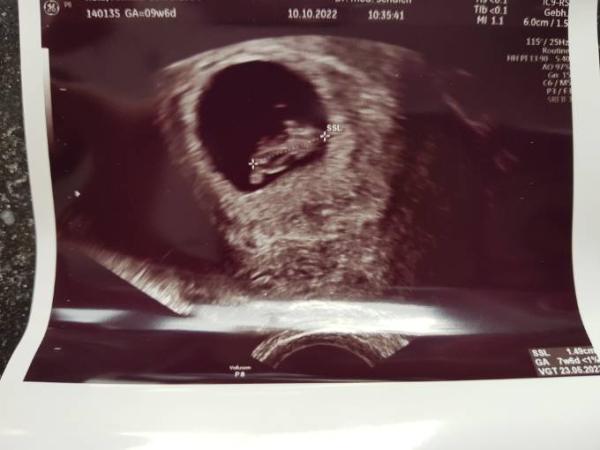

Das war mein 8+3 und jetzt bin ich in der 11.

Bild zu